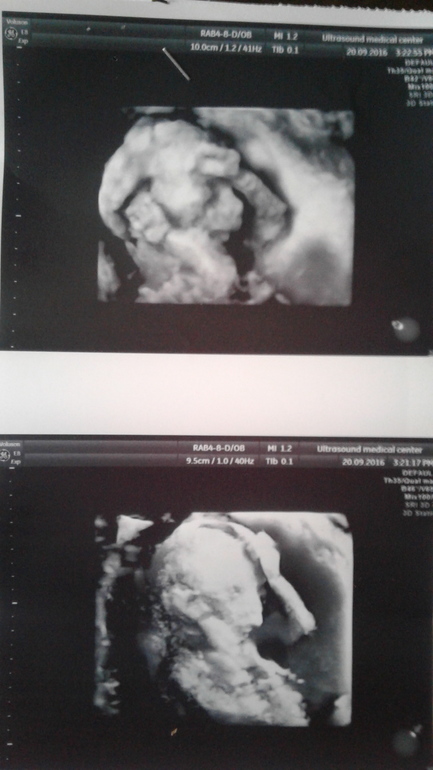

УЗИ, КТГ, доплерПосле перенесенных заболеваний и кучи выпитых лекарств прямая дорога на встречу с Чудом. Все у нас в норме! Уррраааа! Опережаем срок на 4 дня. По Узи нам ровно 17)

Подтвердили нам Дениску. 3 д это здорово!!!

Иииии! Поздравляю, Натусь! Я себе их именно такими и представляю на нашем сроке, худенькими. Знаешь, а твой на фото похож на облачко.